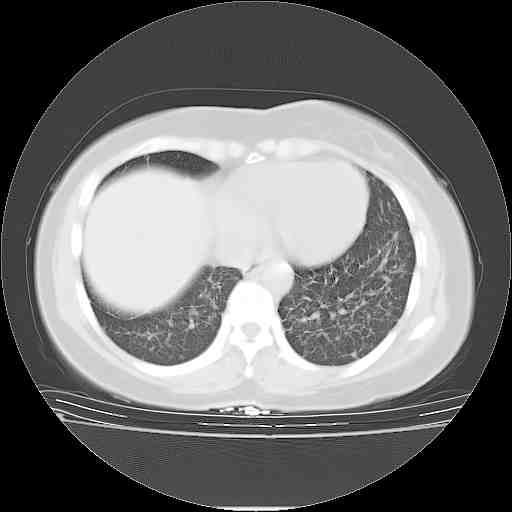

下面是今天刚刚做的,在上海治疗,吃了家属也说不清的一种药,一个月1万左右,

考虑  腺癌肺内转移,治疗较前病灶缩小、减少

肺癌并肺内转移,这种疾病治疗后在影像上看略有好转,不是很显著,但是肿瘤治疗效果影像只是一方面。

支持肺癌并肺内淋巴管炎,  原发灶小了,但转移较前片明显了.

支持右肺下叶周围型肺癌并肺内淋巴管炎,  原发灶小了,但转移较前片明显了.。

标准的细支气管肺泡癌呀!治疗后病情有所控制,也没治愈的迹象!

支持右肺下叶周围型肺癌并肺内淋巴管炎;病灶有所控制。